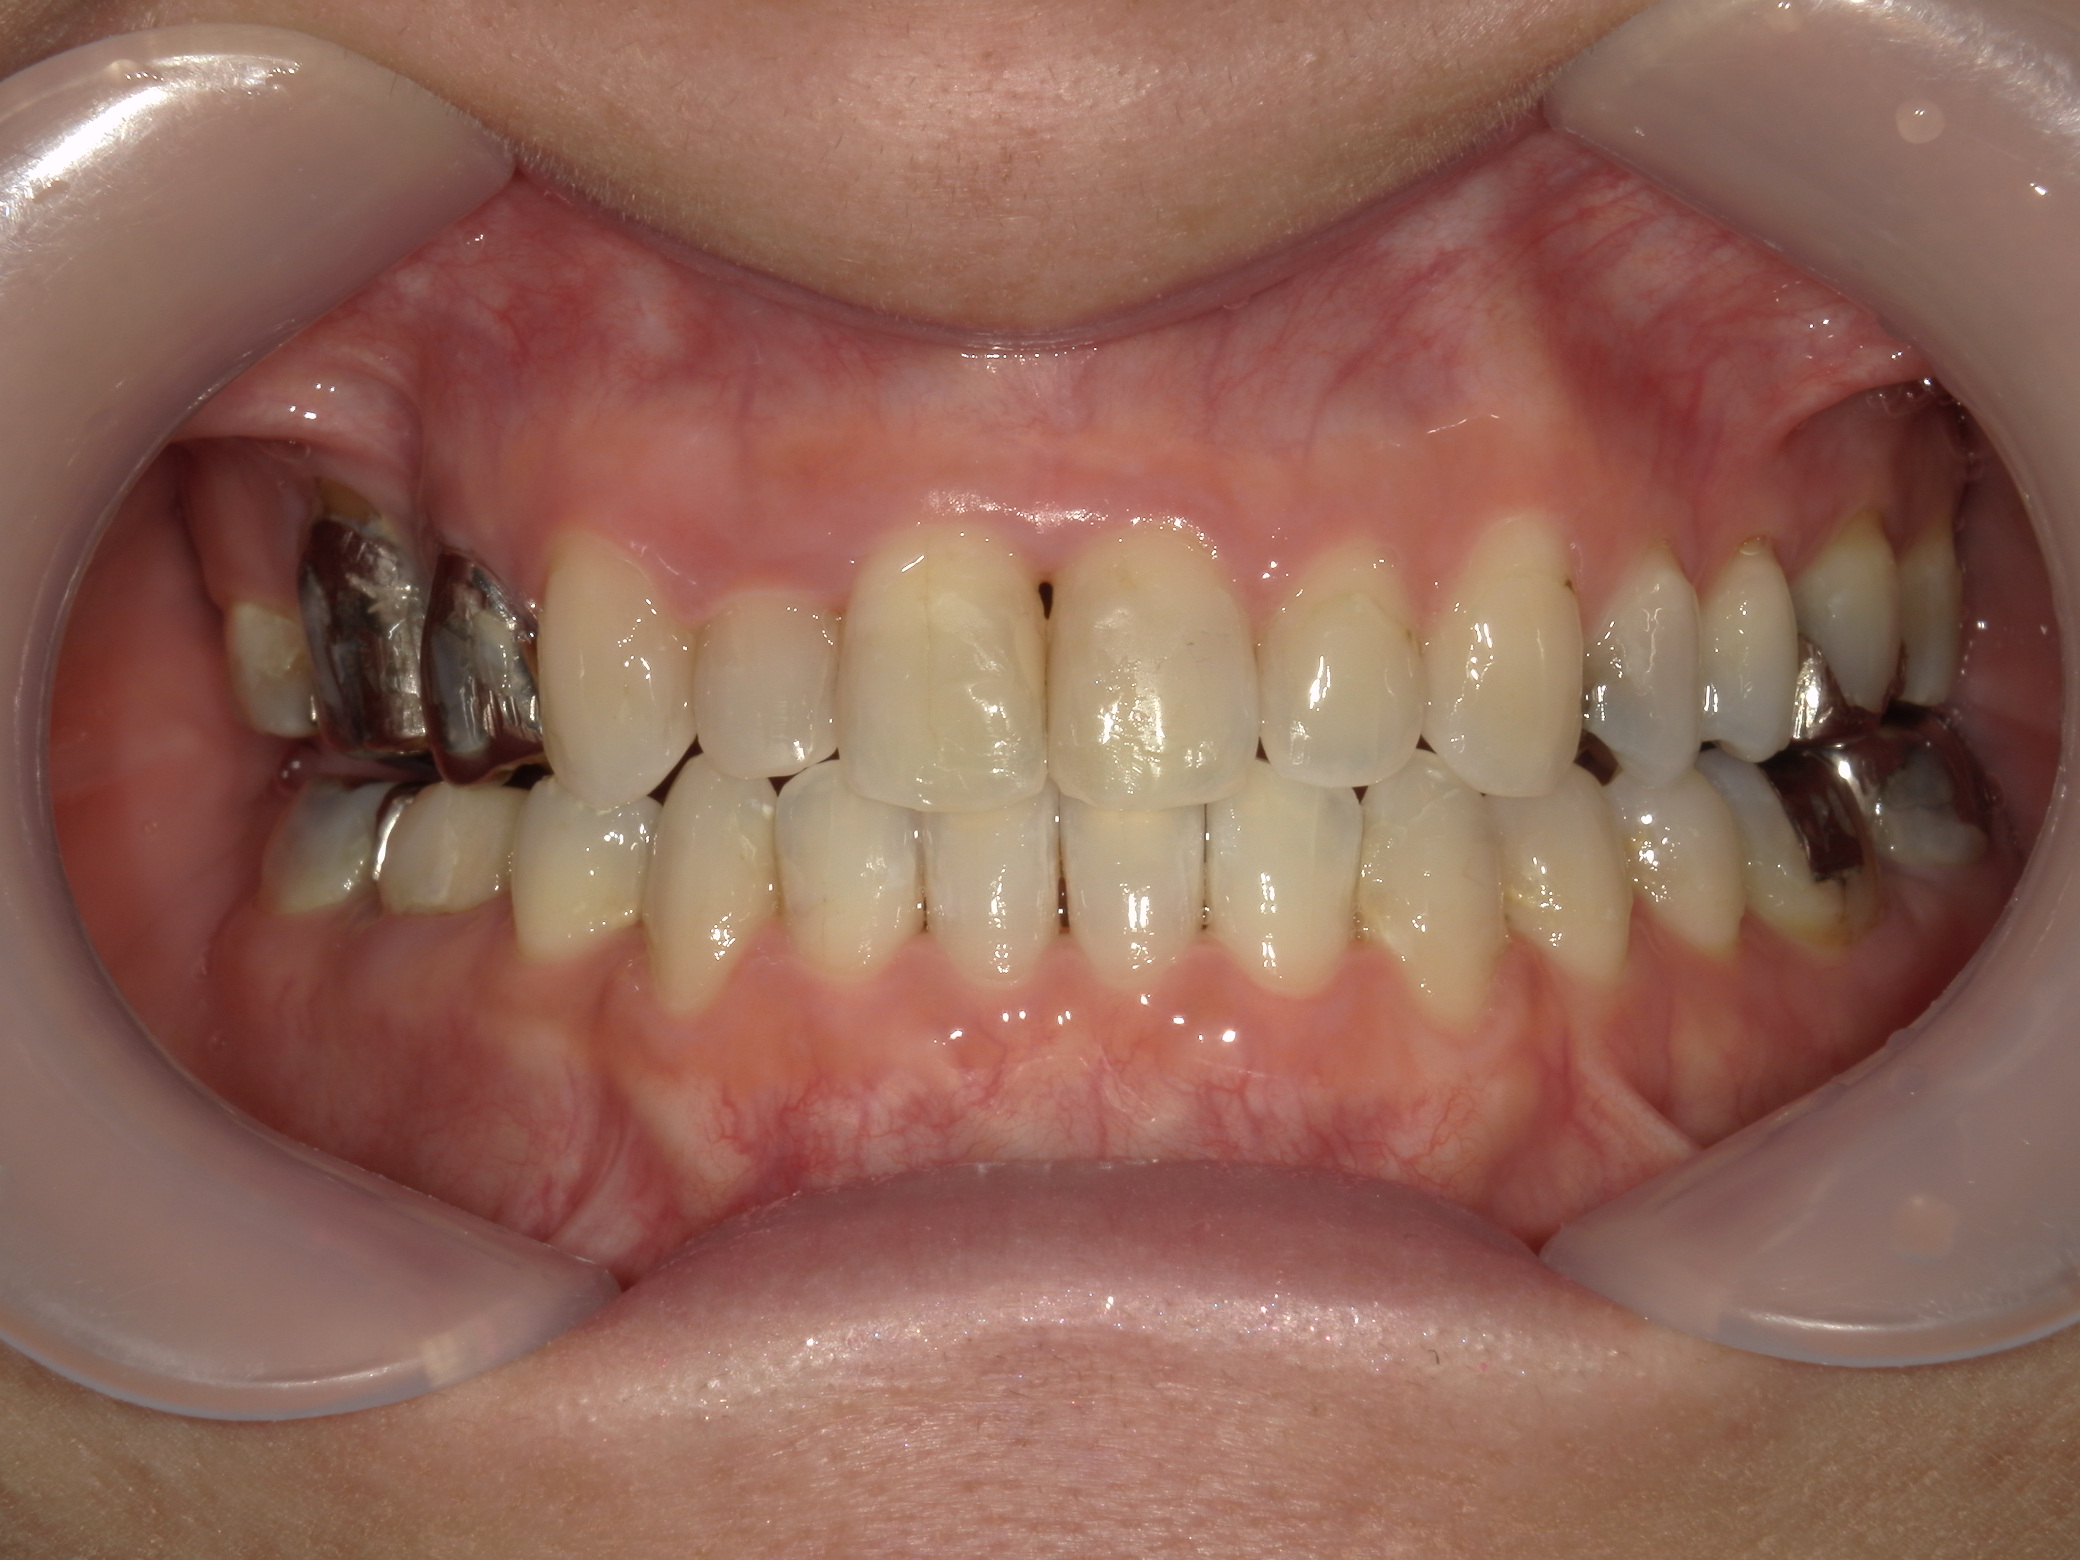

主訴: 受け口、歯並びが気になる。

①患者様はインビザライン矯正をご希望でしたが、上顎骨が小さく、受け口になっているので、インビザライン矯正で治療するために「骨切断OPE」「矯正装置(MSE+フェイスマスク)」で上顎骨を拡大しました。

②右上前歯が内側に入っているため、歯列に入る隙間を作るためにワイヤー矯正を併用し、右上前歯を出しました。